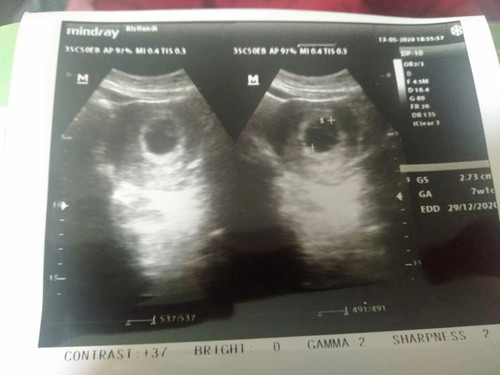

usg 7week

Assalamualaikum bunda, disini ada yg usg 7week baru kelihatan kantungnya aja belum kelihatan janin nya. Kata dokter harusnya udah terlihat janin nya terus saya disuruh untuk periksa lagi 2 minggu kedepan. Bagi pengalaman nya ya bun, trmksh

Baca lagiDokternya aneh berarti bun, emg usia kandungan 7 week mah baru keliatan kantung janinnya aja. Udah nanti cek lg pas udah 12 week aja bun aku waktu itu gitu. Cm bedanya dokterku blg usia 6-8 week memang baru terlihat kantungnya, rajin minum asam folat ya bun Bismillah berkembang janinnya